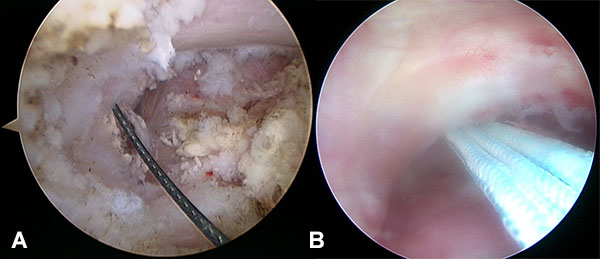

Con el paciente con bloqueo interescalénico y en posición de silla de playa con el brazo sin tracción en 10 a 20 grados de flexión y 20 a 30 grados de abducción, se introduce artroscopio por un portal posterior estándar y se realiza una artroscopia diagnostica en busca de lesiones asociadas. Se realiza un portal antero-inferior justo por encima del tendón del subescapular levemente más lateral de lo convencional con técnica de afuera-adentro y con dirección a la base de la coracoides, se realiza la colocación de cánula de 8,25 mm. Se realiza la apertura del intervalo de los rotador con shaver y electro bisturí artroscópico hasta la visualización de la punta y la base de la coracoides. Luego realizamos un nuevo portal percutáneo anterosuperolateral con técnica de afuera adentro y lo establecemos como nuevo portal de visión. Completamos la exposición de la base de la coracoides en la unión con la cara anterior del omoplato (fig. 1A) Se introduce el compás guía para AC TightRope o sistema DogBone por el portal antero inferior y se lo posiciona centrado en la coracoides a nivel de la unión de la base de la coracoides con la cara anterior del omoplato en 70 a 90 grados de angulación (fig. 1B). Se realiza un abordaje longitudinal de 2 a 3 cm a nivel del foco de fractura, se limpia foco de fractura, se reseca tejido interpuesto y se realiza la reducción de la fractura y fijación transitoria con clavijas de 1,6 mm, se controla reducción por radioscopia (fig. 2). La guía del compas es posicionada entre 25 y 30 mm medial a la articulación acromioclavicular y centrada en la clavícula para evitar lesionar la cortical anterior o posterior. Se realiza la perforación de la clavícula y la coracoides con drill pin canulado de 3 mm atravesando 4 corticales para pasar a través de la clavícula y coracoides visualizando posicionamiento por radioscopia, y control por artroscopia de la salida del drill pin en la base de la coracoides, se retira el pin del drill canulado y se introduce un alambre de nitinol que se recupera por el portal antero inferior (fig 3). Se retira el drill canulado dejando el alambre de nitinol. Si vamos a utilizar sistema AC TightRope debemos desmontar ambos botones del FiberWire y montar dos suturas FiberTape en el botón longitudinal para pasar a través del túnel coracoideo y clavicular solo los cuatro extremos suturas. Se montan los 4 extremos de las suturas FiberTape del implante subcoracoideo en el alambre de nitinol y se realiza el pasaje del mismo de distal a proximal (fig. 4). Bajo visión artroscópica directa se comprueba el pasaje y posicionamiento del botón subcoracoideo (fig. 5). Se realiza la reducción de la fractura aplicando presión inferior sobre el fragmento proximal de la fractura y contrapresión superior desde el codo para ayudar a reducir la fractura. Una vez reducida la fractura bajo control radioscópico se completa la fijación del botón clavicular del sistema AC TightRope o DogBone y con sutura FiberTape transósea se incorpora el fragmento distal de la fractura a la reconstrucción (fig. 6).

Figura 4: Pasaje de Nitinol y Suturas FiberTape pasaje del implante Subcoracoideo de distal a proximal.

Figura 5: Posicionamiento del botón subcoracoideo.